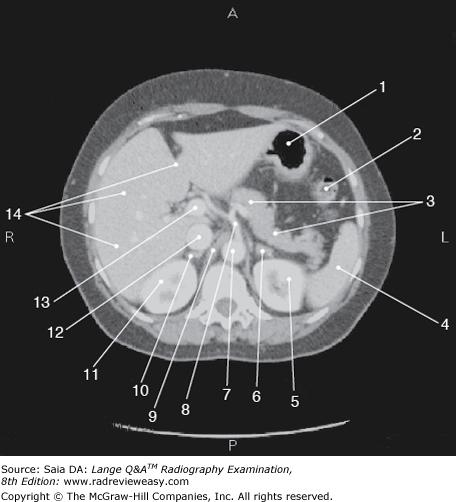

Which of the following is represented by the number 3 in the figure below?

Aorta

The figure below illustrates a sectional image of the abdomen. Which of the following is represented by the number 13?

Portal vein